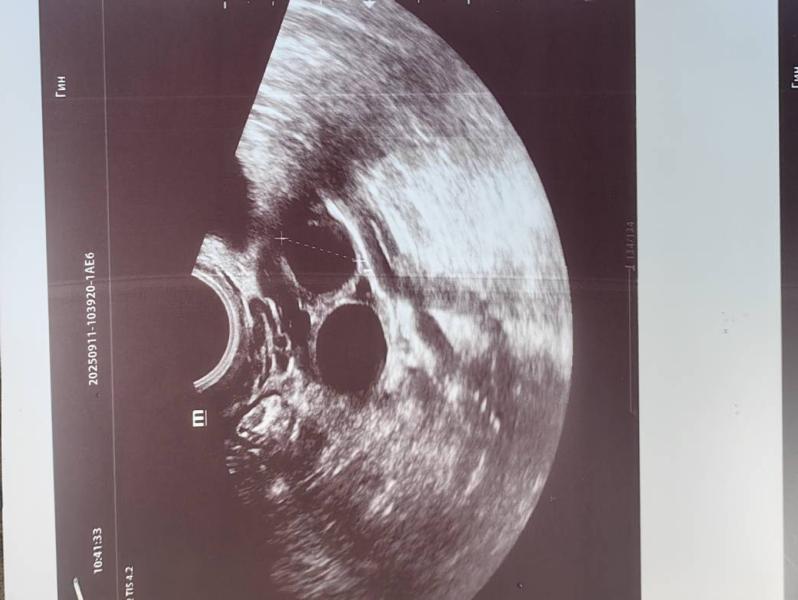

Я на стимуляции . 2дф с лева 20мм и 16.7мм

И один справа но маленький 11,7мм

Сегодня уколола укол хгч 5000ме.

Ещё подключили эстрожель. Какие шансы что лопнут оба? Ведь размеры разные .